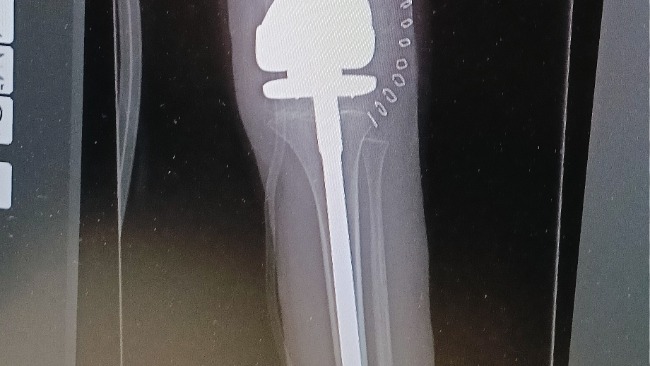

Kochani, czasami pojawia się dzień , który ścina nas z nóg . Tak było , gdy dowiedzieliśmy się o diagnozie naszego 7 letniego Filipka. Mamy złośliwego guza kości udowej lewej nogi , opisanego jako mięsak kościopochodny-high gradem conventional central osteosarcoma.

Zaczynamy drogę poprzez chemioterapię . Czeka nas jeszcze niebawem operacja , podczas której Filipek będzie miał wstawioną Endoprotezę zamiast części kości udowej . Przed nim jeszcze długa droga do wyzdrowienia oraz niezliczone godziny pracy nad powrotem do pełnej sprawności .

Po udanej operacji Filipek wraca do sił❤️🩹

Mimo wymagającej i bolącej rehabilitacji nie poddaje się i walczy ,żeby na wiosnę jeździć na rowerze 🚴 Od wtorku zaczynamy kolejny "turnus" chemioterapii, połowa za nami 💪💙